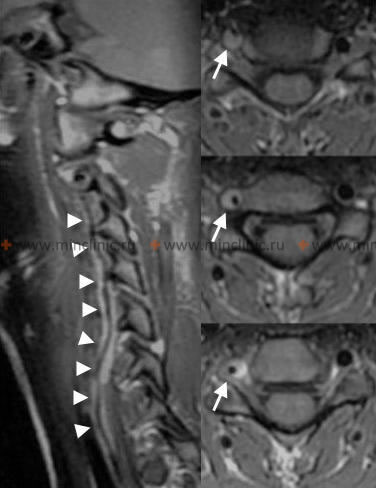

- თავის ტვინის მრტ: არჩევის ვიზუალიზაციის მეთოდი. დიფუზია-შეწონილი ვიზუალიზაციის (DWI) რეჟიმები ძალიან მგრძნობიარეა მწვავე იშემიის გამოსავლენად წუთებიდან საათებში, ნათლად აჩვენებს ინფარქტებს მოგრძო ტვინსა და ნათხემში. FLAIR რეჟიმები ეხმარება ინფარქტის ხანდაზმულობის შეფასებაში, ხოლო GRE/SWI რეჟიმებს შეუძლიათ გამოავლინონ მცირე სისხლჩაქცევები ან დისექციის ნიშნები.

- სისხლძარღვოვანი ვიზუალიზაცია: გადამწყვეტია ძირითადი მიზეზის დასადგენად (ოკლუზია, სტენოზი, დისექცია) [4, 5].

- თავისა და კისრის მრა (მაგნიტურ-რეზონანსული ანგიოგრაფია): არაინვაზიური ალტერნატივა, კარგია სკრინინგისთვის, მაგრამ შეიძლება ნაკლებად ზუსტი იყოს, ვიდრე კტა/დსა სტენოზის ხარისხის ან მცირე დისექციის შესაფასებლად. მაღალი ველის მრა (მაგ., 3 ტესლა) გვთავაზობს გაუმჯობესებულ რეზოლუციას.